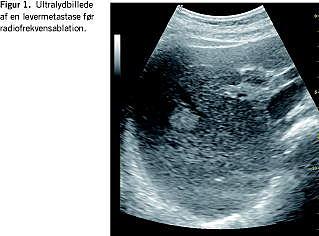

Kemisk ablation med injektion af absolut alkohol i tumorer var tidligere den mest udbredte behandling især ved HCC, men sammenlignende RCT viser, at termisk ablation er overlegen på de vigtigste effektparametre: cancerfri overlevelse og samlet overlevelse [3, 4]. Dette har betydet, at termisk ablation til såvel HCC som metastaser anses for at være standardlokalbehandling. Alkoholinjektionsbehandling kan dog anvendes til HCC, som er for store eller uregelmæssige til termisk ablation. Den nyeste RCT af HCC tyder også på, at man ved behandlingen af HCC bør benytte radiofrekvensablation (RFA) og alkoholinjektion som kombination frem for RFA alene [5]. De termiske ablationsteknikker omfatter RFA, mikrobølgebehandling (MCT), laserinduceret termoterapi, cryoterapi og højintensitetsfokuseret ultralyd. De tre sidste teknikker tilbydes p.t. ikke i Danmark. RFA er den mest udbredte behandling. Der er ingen RCT, der viser, hvilken termisk behandling der er bedst til hverken HCC eller metastaser, men i langt de fleste publicerede undersøgelser har man anvendt RFA. Teknik, sikkerhed, komplikationer, effekt og resultater ved brug af RFA er derfor den bedst beskrevne i litteraturen. To danske undersøgelser vedrørende brugen af RFA ved levertumorer er tidligere publiceret [6, 7]. Langtidsopfølgning af resultaterne af brug af RFA hos danske patienter viste en medianoverlevelse på 32 måneder og en fireårsoverlevelse på 26% for KRC-metastaser, hvilket er på niveau med overlevelsesresultater internationalt ved brug af RFA og ved kirurgisk leverresektion [8]. RFA har den fordel, at den kan udføres såvel minimalt invasivt som perkutant eller laparoskopisk vejledt af ultralyd eller computertomografi samt ved åben intraoperativ procedure (Figur 1 og Figur 2 ). MCT og cryoterapi udføres derimod primært intraoperativt og dermed mere invasivt. Generelt bliver der fundet flest metastaser, der kan behandles, når proceduren fortages intraoperativt eller laparoskopisk, men der foreligger ingen RCT-data, hvor man sammenligner applikationsmetoderne. Valget må derfor afhænge af patientens risiko ved en invasiv procedure og forandringernes placering iht. metodens mulighed for nøjagtig applikation af RF-energien til tumorerne. Der er i dag flere tilgængelige udstyr til RFA, men der findes ingen sikre data fra RCT, der kan afgøre, hvilket udstyr der giver de bedste resultater. Den population af patienter, der tilbydes lokal behandling i Danmark, er primært patienter med metastaser efter KRC. Der foreligger ingen data fra RCT om, hvilket antal metastaser man kan og bør behandle, og om patienterne skal behandles med kun RFA eller i kombination med kemoterapi. For tiden er der et multicenterstudie i gang under EORTC - CLOCC-studiet, hvor man behandler op til ti metastaser efter KRC og randomiserer til kemoterapi alene eller kemoterapi og RFA [9]. Dette studie kan forhåbentlig i fremtiden give os mere sikre retningslinjer for behandlingerne. Indtil da bør behandlingen gives under løbende opfølgning, hvor det er vigtigt, at de enkelte patientforløb bliver vurderet individuelt og tværfagligt.